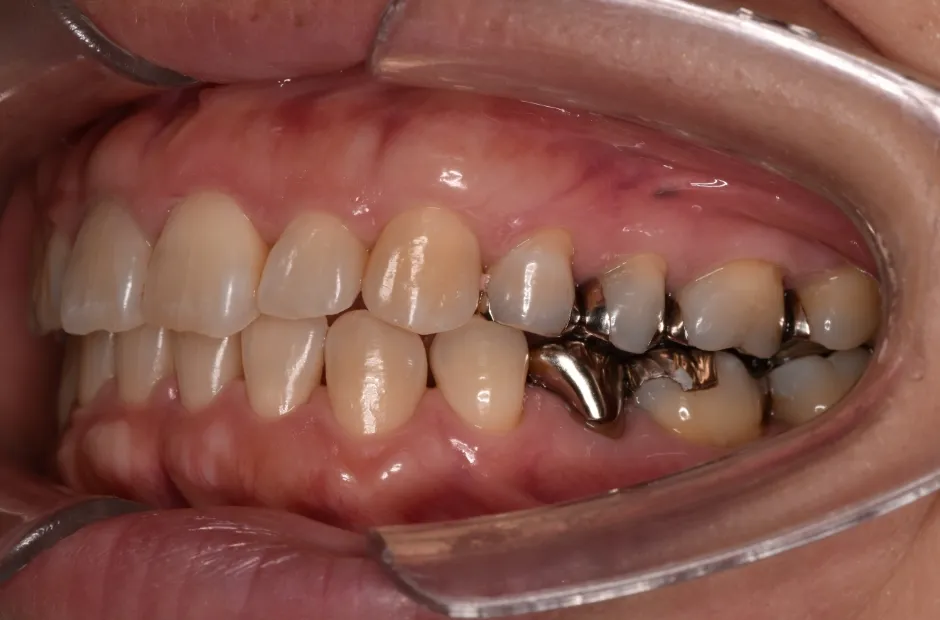

叢生

| 診断名・主訴 | 叢生 |

|---|---|

| 年齢・性別 | 43歳・女性 |

| 治療期間・回数 | 2年7か月 27回 |

| 治療に用いた主な装置 | 舌側矯正 |

| 抜歯部位 | 両顎4,4 |

| 治療費 | 100万円(税抜) |

| リスク・副作用 | 装置による違和感・疼痛・歯肉退縮・歯根吸収・虫歯のリスクなど |

治療前